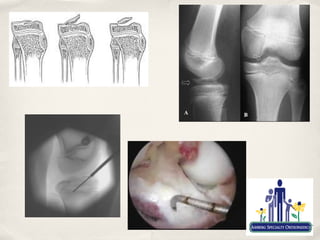

Discoid Meniscus

✤   Congenital variant present at birth

✤      Three types

✤      Most often assymtomatic

✤      In the young child may present as dramatic snapping, either

audible or palpable

✤      May result in abnormal biomechanics of knee

✤   Treatment

✤   Assymptomatic children do not require treatment

✤   Will occasionally tear in older child or adolescent

✤   Symptoms of swelling and lateral joint line pain

✤   Saucerization of meniscus and repair/stabilisation

✤   Occasionally associated with OCD of LFC

✤      Addressed as per OCDs

Osteochondritis Dissecans

✤   "Bone-cartilage separation/dissection"

✤   Occurs in Juvenile (5-15) and adult forms (16-50)

✤   More common in males

✤   After skeletal maturity prognosis is much worse

✤   Most often affects lateral aspect of medial femoral condyle

✤   Felt to result from repetitive microtrauma although other

factors probably contribute

✤   Separation of osteochondral fragment highly likely to result

in DJD

✤   Operative

✤      Anterograde or retrograde drilling

✤      Lesion Stabilisation

✤      Microfracture

✤      Cartilage "replacement"

✤           OATS/Mosaicplasty/Autologous

chondrocyte transplantation